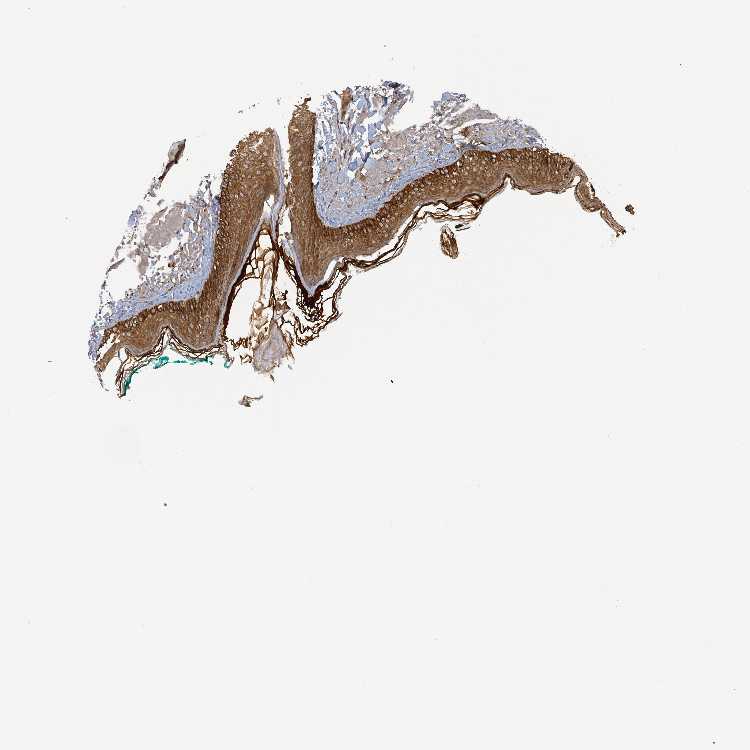

SKIN 1 - Antibody stainingi

Antibody staining in the annotated cell types in the current human tissue is reported as not detected, low, medium, or high, based on conventional immunohistochemistry profiling in selected tissues. This score is based on the combination of the staining intensity and fraction of stained cells.

Each image is clickable and will lead to virtual microscopy that enables deeper exploration of all samples and also displays staining intensity scores, fraction scores and subcellular localization as well as patient and tissue information for each sample.

Antibody HPA051813

Langerhans High

Fibroblasts Not detected

Keratinocytes High

Melanocytes High

SKIN 2 - Antibody stainingi

Epidermal cells High